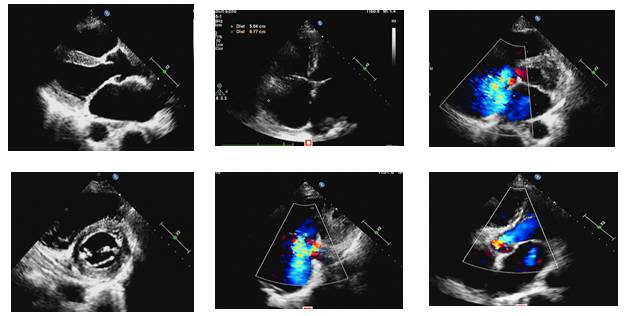

2016-11心脏彩超

◆LA39mm,LV38mm,RA:71x54mm,RV:30mm,FS:25%,EF:50%;

◆二尖瓣退行性变并中重度反流;

◆三尖瓣中-重度反流;

◆轻度肺动脉高压36-41mmHg;

◆主动脉瓣少量反流;

◆心包少量积液较大深度约9mm(心底部)。